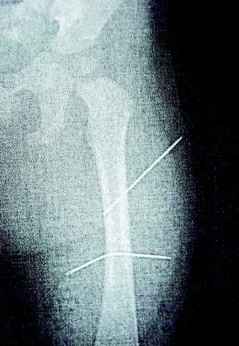

隔月27日,该女子又见外甥女哭闹不停,拿苍蝇拍朝着外甥女背部连打数十下,造成女娃背部瘀伤。经女娃母亲发现后送医救护,院方为女童进行X光片照射后,才发现女娃左大腿里竟有两根缝衣针。